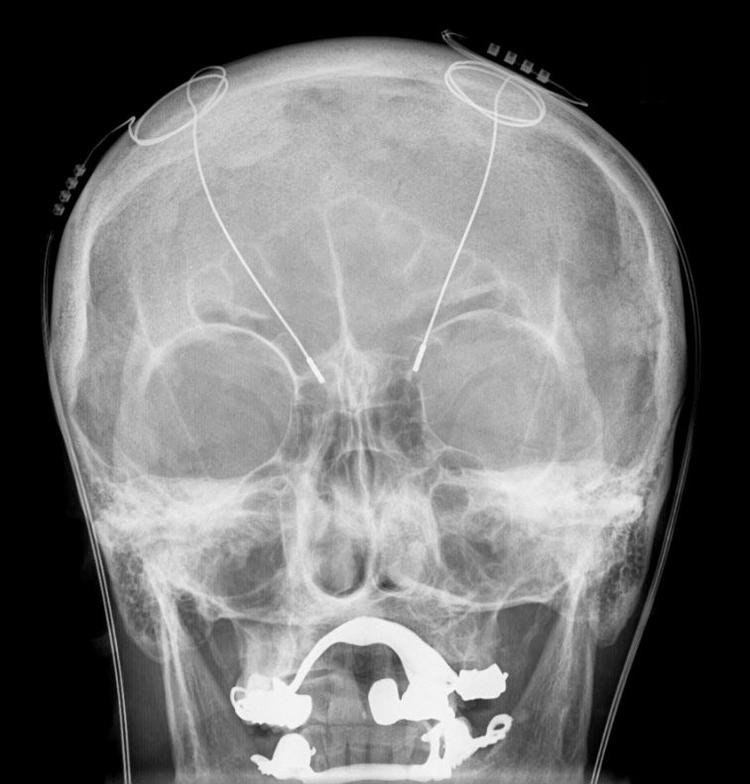

Han fortæller til et kamera med veloplagt britisk accent, hvordan han har fået en elektrode opereret ind i hjernen, der er forbundet til et batteri, som sidder under huden i hans venstre bryst.